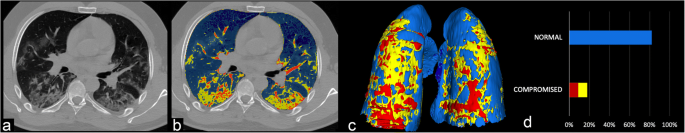

Automated Quantification Of Ct Patterns Associated With Covid 19 From Chest Ct Radiology Artificial Intelligence